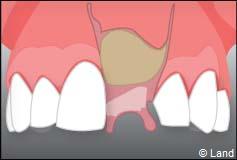

À l’issue de sa mise en place chirurgicale, une bague de cicatrisation en titane peut être directement vissée sur l’implant. Ainsi une seconde chirurgie ne sera pas nécessaire pour découvrir l’implant.

La technique en une seule étape chirurgicale n’est pas toujours possible, c’est à votre chirurgien-dentiste de prendre la décision.

Pour finir, une prothèse sera mise sur cet implant qui se comportera comme une racine artificielle.